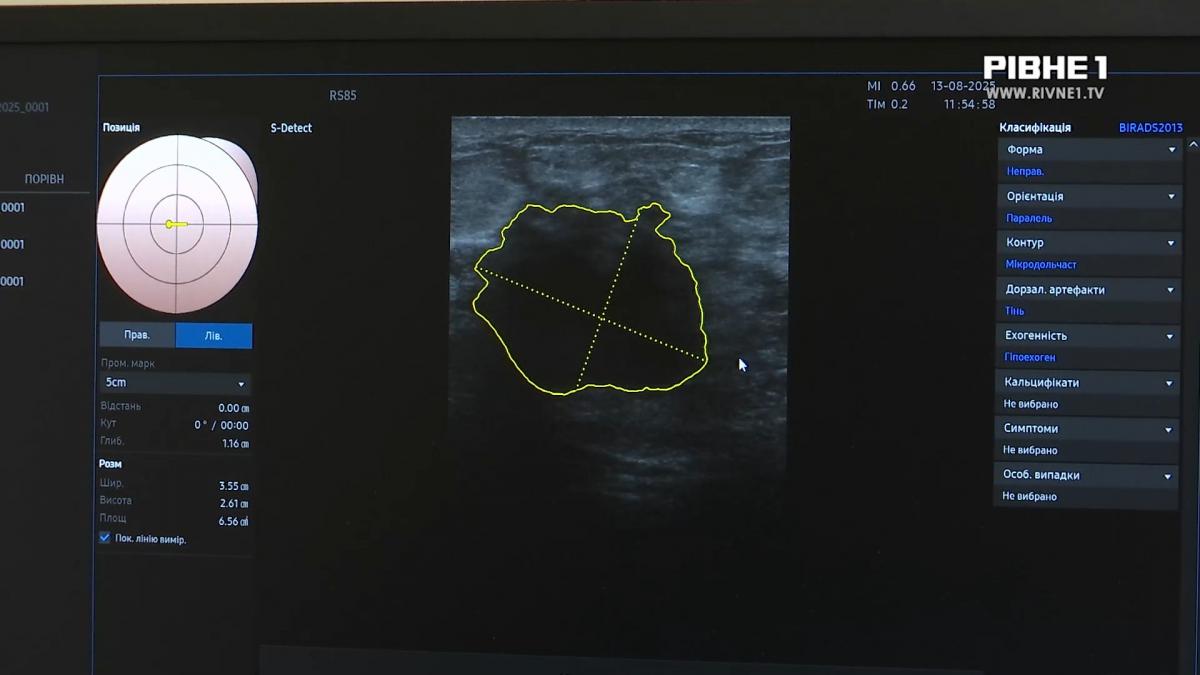

Коли ми знаходимо пухлину, ШІ він промальовує і виставляє свій попередній висновок, що це може бути злоякісність.

Ще одна головна функція приладу полягає в тому, що система штучного інтелекту допомагає точніше розрізняти доброякісні й злоякісні утворення, а також бачити кровотік навіть у найдрібніших судинах пухлин. Це стало можливим лише завдяки апарату. Проте лікар Максим Куба зауважує: він не замінює фахівця, а лише допомагає в діагностиці.

Він допомагає у виявлені деяких новоутворень і може їх класифікувати як доброякісні або злоякісні, але сам один ШІ без лікаря нічого не може зробити, - зазначає Максим Куба.